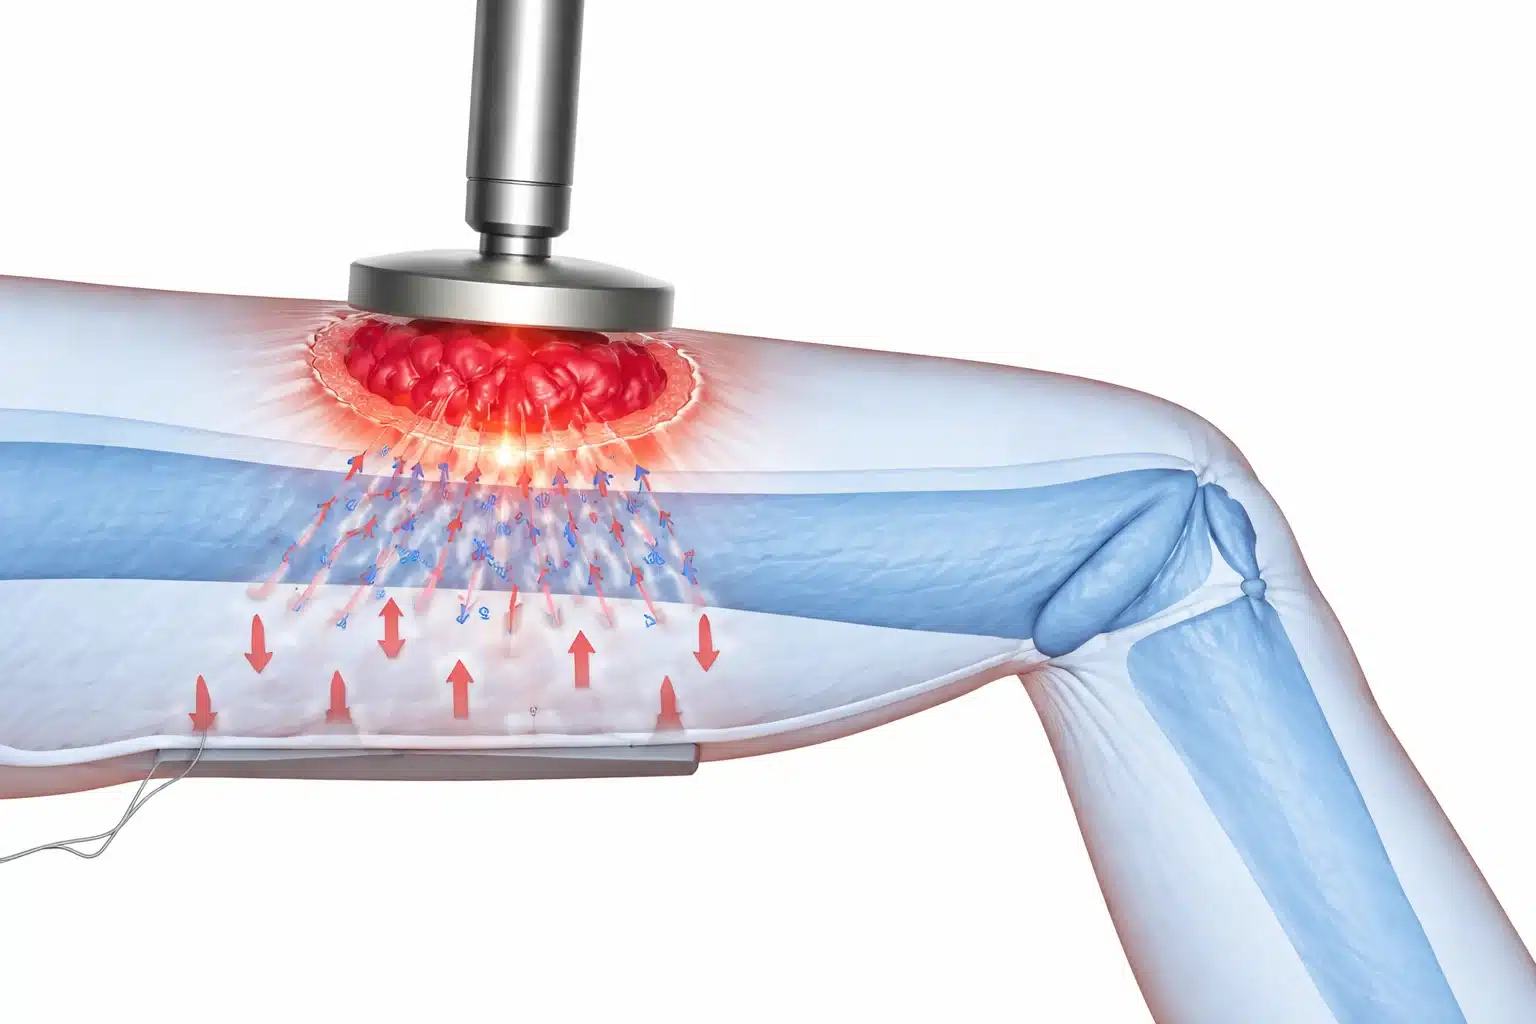

¿Qué es la electroterapia?

Por definición es la aplicación de energía electromagnética al organismo (en diferentes modalidades), con el fín de producir unas reacciones biológicas y fisiológicas que tendrán como objetivo final un efecto terapéutico.

Electroestimulación

Equipos Combinados